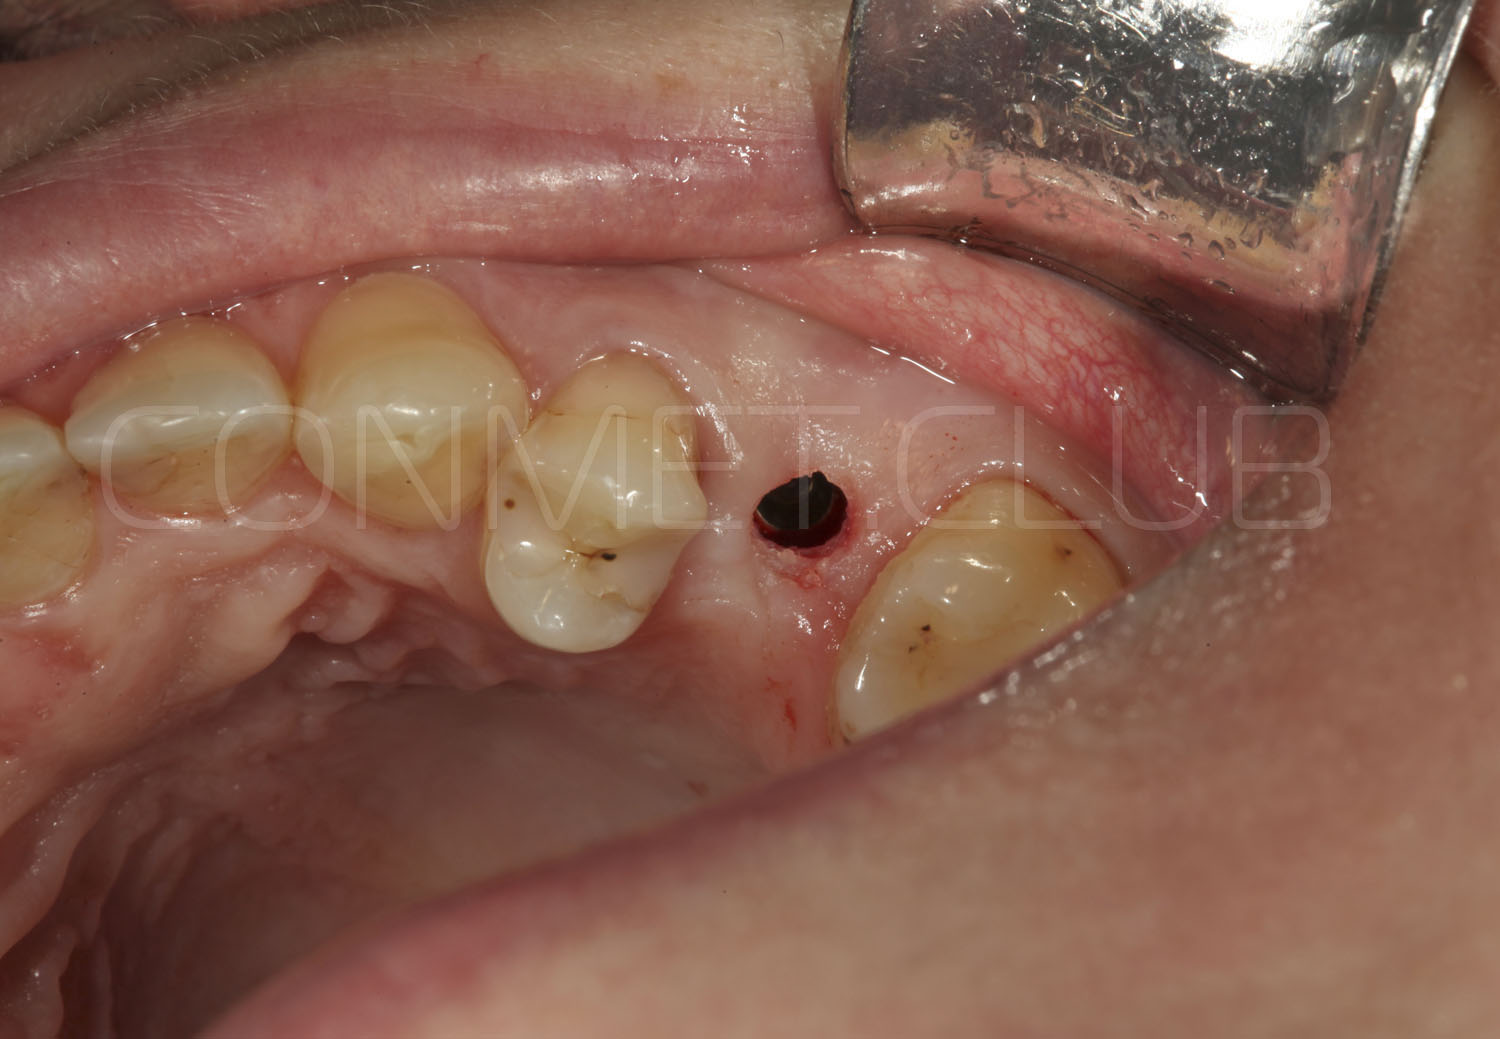

Обязательным условием работы с направляющими шаблонами является проверка точности посадки позиционирующего шаблона на апроксимальные зубы. Посадка не должна быть чрезмерно плотной и шаблон должен располагаться на зубах без баланса.

Препарирование ложа производится через слизистую оболочку, без отслаивания лоскутов, в таком случае контроль глубины препарирования следует проводить с учётом толщины слизистой оболочки и высоты направляющей втулки.

Направляющие втулки нового типа имеют цветовую маркировку (с диаметром отверстия 2,2 мм - серебристого цвета и 2,8 мм - золотистого цвета), а также одинаковый внешний диаметр, что позволяет использовать 2 одинаковых шаблона, но с втулками разного диаметра.

Характерной особенностью новых втулок является их фиксация в шаблон без использования клеев или адгезивов. Это значительно упрощает работу при фиксации втулок в шаблон и абсолютно исключает попадание фиксирующего клея внутрь втулок.